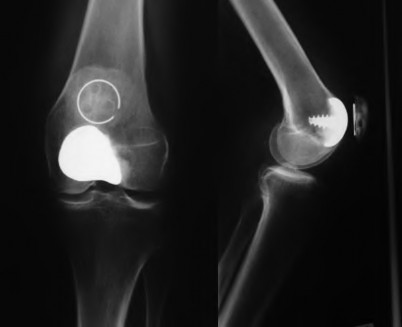

A 64-year-old woman with osteoarthritis underwent bilateral total knee replacement 3 years ago. Current radiographs are shown in Figure A. She reports a 3-month history of bilateral knee pain while at rest and increasing swelling in the knees. Her ESR and CRP are elevated and bilateral knee aspiration cultures reveal Staphylococcus aureus. What is the most likely outcome if the patient undergoes simultaneous, bilateral knee resection arthroplasty with cement spacer and a course of intravenous antibiotics?

This patient presents with bilateral total knee arthroplasty infection.

Wolff et al report Level 4 evidence of 18 patients followed an average of 5 years after bilateral TKA infection. Eleven patients were initially treated with attempts to salvage the original prosthesis (polyethylene l liner exchange, I&D, IV antibiotics and chronic oral suppressive antibiotics. With prosthesis retention, 9/11 (81%) developed recurrent infection at a mean of 15 months. The other 10 patients initially underwent resection arthroplasty with cement spacer and a course of IV antibiotics. Seven of the 10 (70%) underwent reimplantation at a mean of 3 months (6 weeks to 5 months) and none of the patients required revision at mean of two years follow up. Satisfaction rates were significantly higher among this group of patients. The authors advocate the protocol of bilateral TKA resection arthroplasty with cement antibiotic spacer and course of IV antibiotics followed by prosthesis reimplantation.